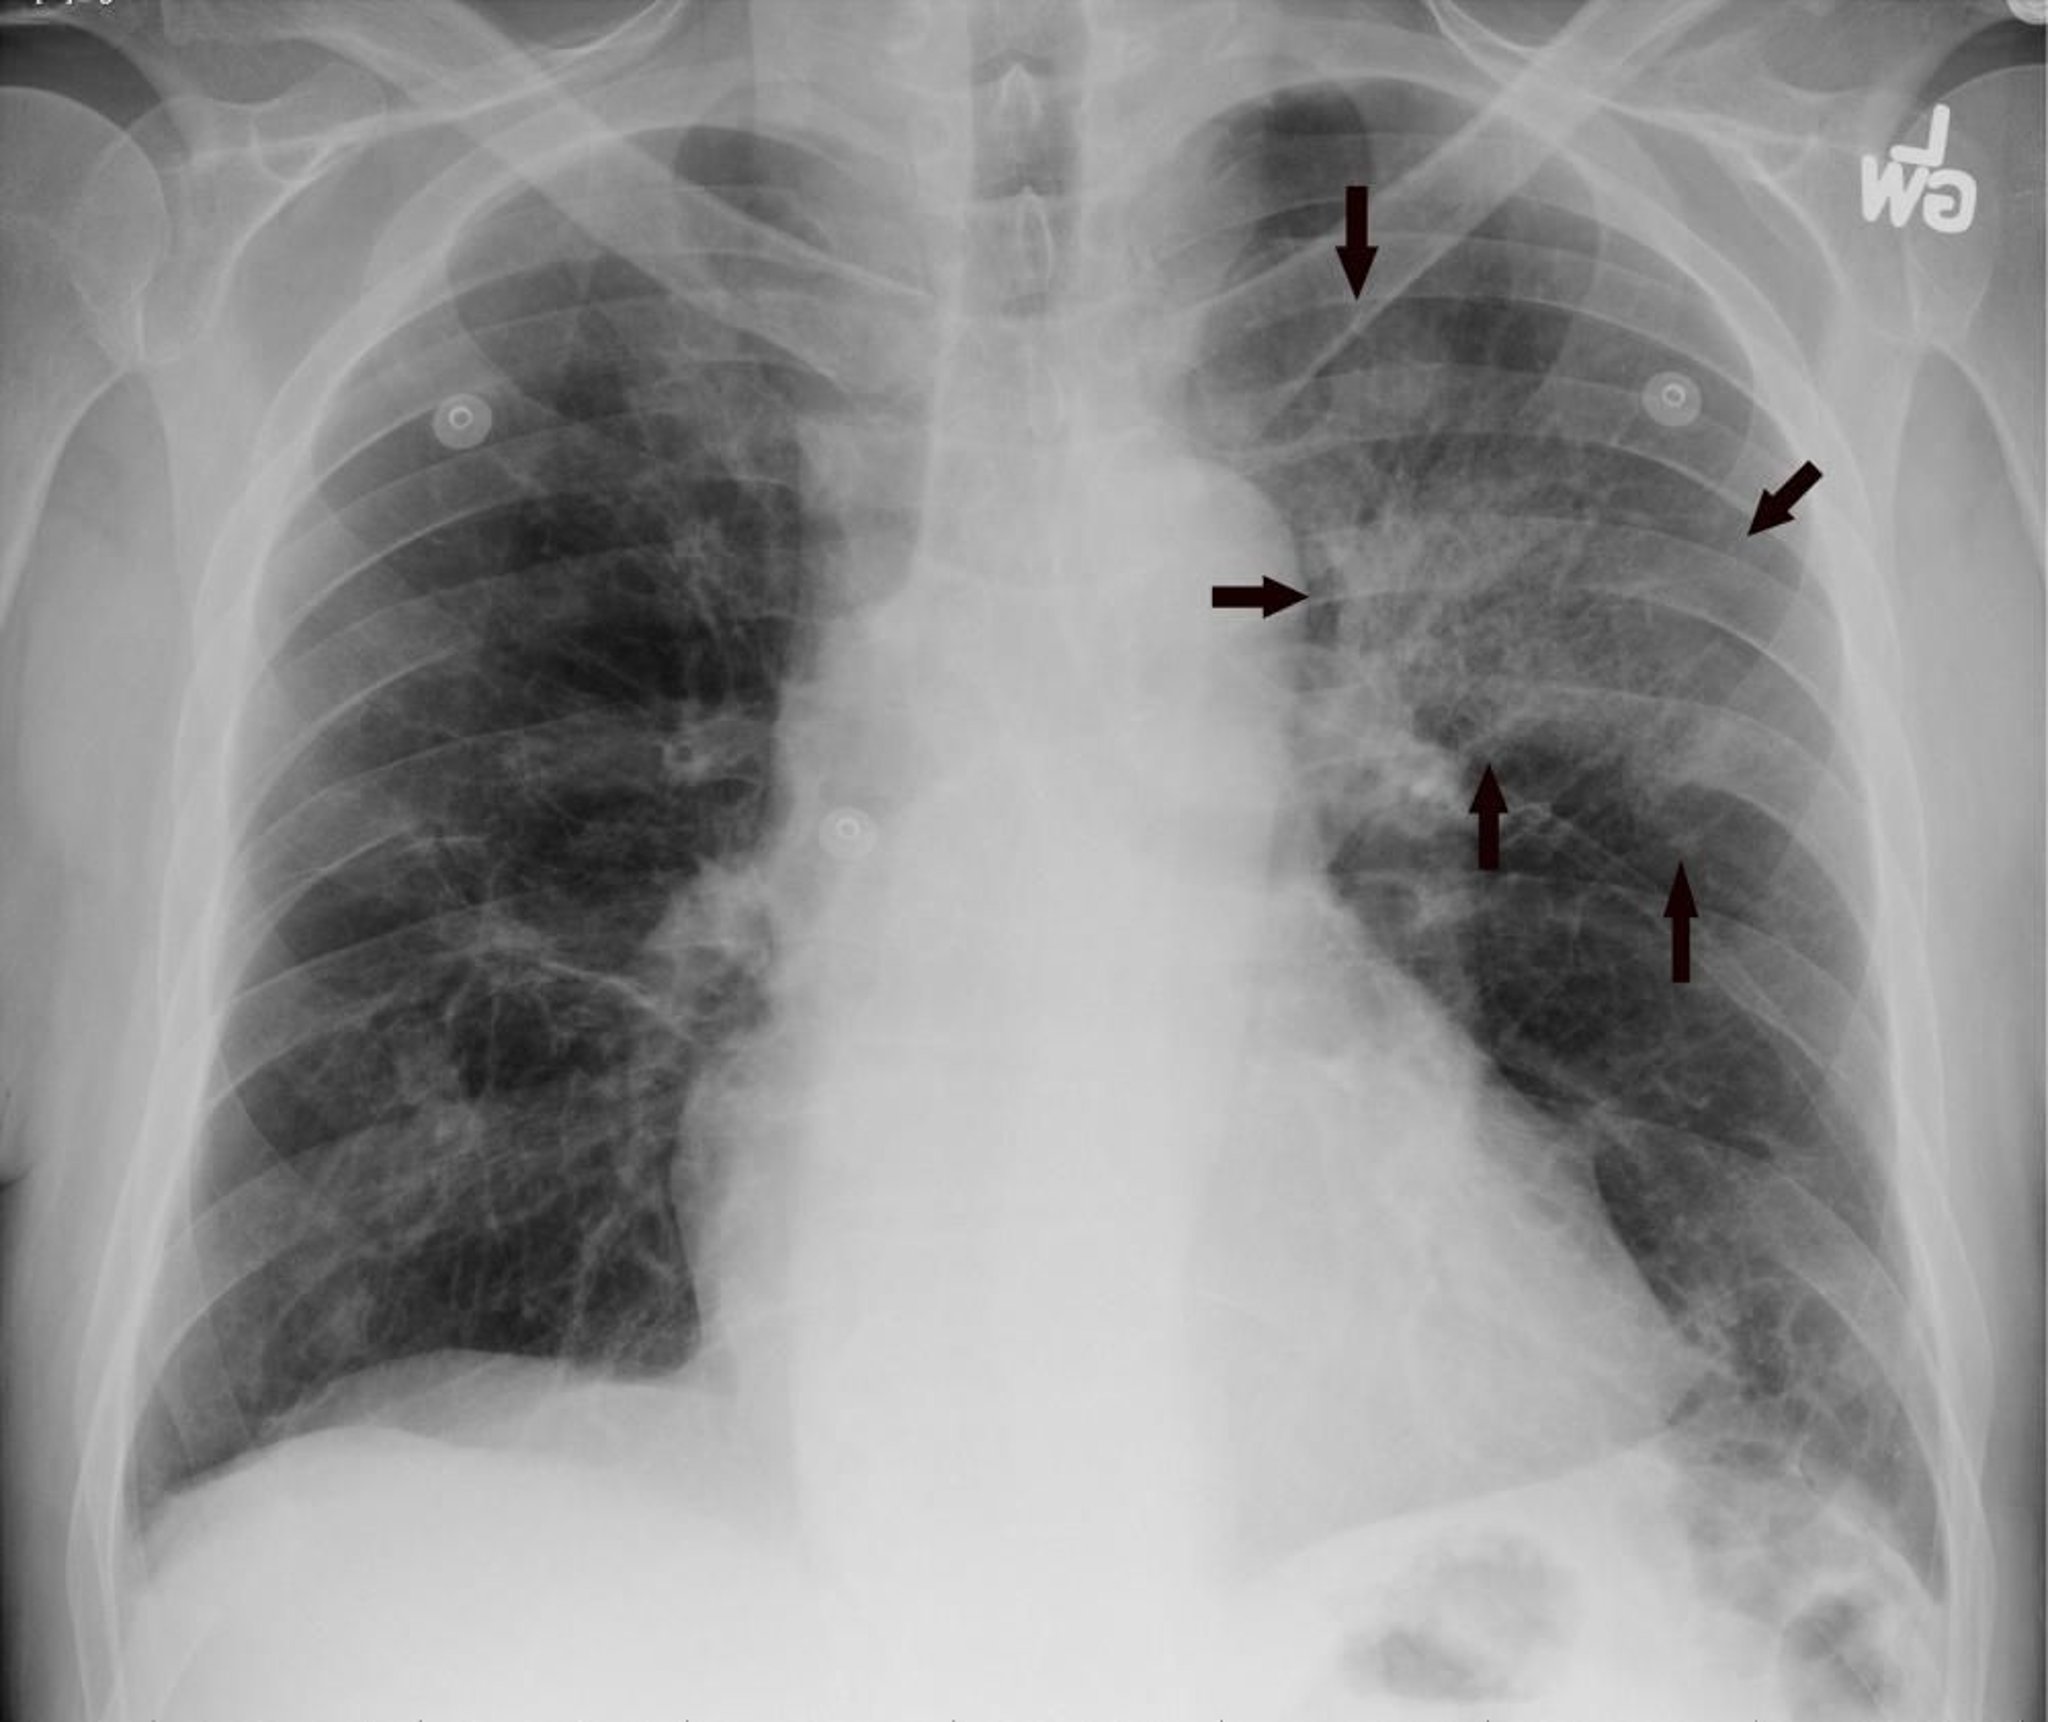

La radiographie de face du thorax montre un infiltrat du lobe supérieur gauche compatible avec une pneumonie (flèches).

Image courtoisie de Hakan Ilaslan, MD.